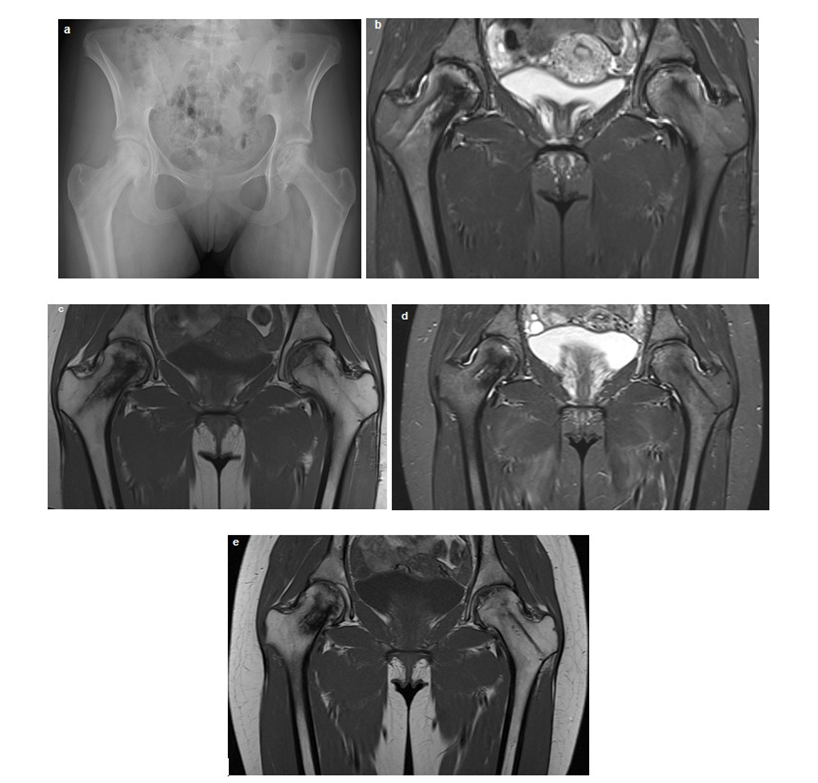

Regular clinical and imaging follow-up have been performed to date showing complete restoration of joint functionality. Three years after the procedure, the girl shows no functional limitation in the hip joints and engages sport activities, and MRI confirmed substantial stability of the condition and stabilization of the cortical profile of the hips (Figure 2).

Figure 2: Radiographic and Magnetic Resonance Imaging (MRI) Follow-up of Bilateral Femoral Head Osteonecrosis. (a) Hip X-ray, approximately 12 months post-surgical intervention, demonstrating preserved femoral head height and morphology despite residual bone structural damage, characterized by areas of resorption and sclerosis, more pronounced on the left side. (b, c, d, e) Sequential coronal MRI images, including STIR and T1-weighted (T1W) sequences, acquired at 16 months (b, d) and 3 years (c, e) post-surgery. These images illustrate progressive improvement in bone marrow signal within the femoral heads, with a notable reduction in bilateral bone marrow edema and stabilization of structural bone changes.